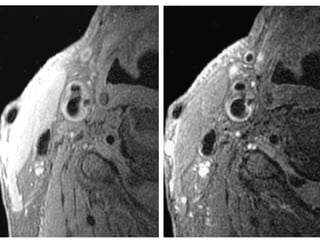

The document describes the Pathway MRITM Carotid Array coil, which is designed for high resolution imaging of small soft tissue structures like the carotid arteries. It provides images showing atherosclerotic plaque buildup in the carotid arteries, including plaque in the common carotid artery, carotid bifurcation, and internal carotid artery stenosis and plaque.